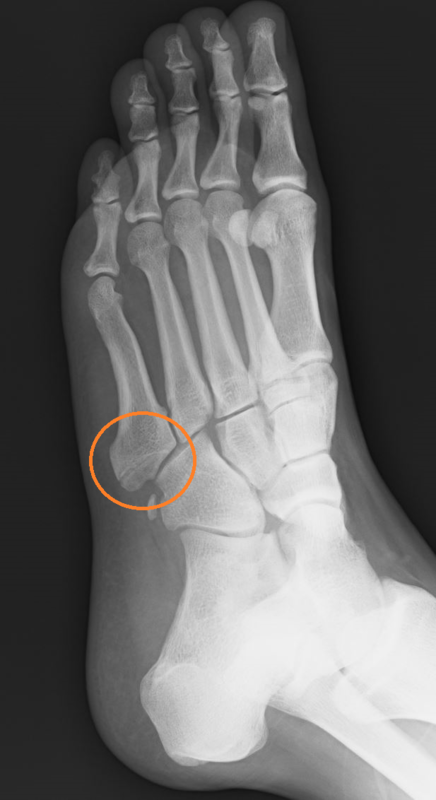

3回体外衝撃波施行し、1か月前より骨折部が癒合してきました。

体外衝撃波は3回で終了し、骨折部に負担がかからないようにインソール(中敷き)を作成しました。